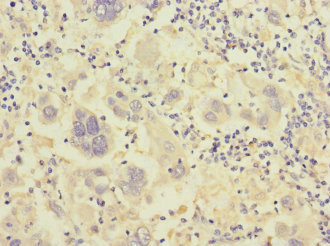

CSB-PA011891ESR1HU

Immunohistochemistry of paraffin-embedded human liver cancer using CSB-PA011891ESR1HU at dilution of 1:100